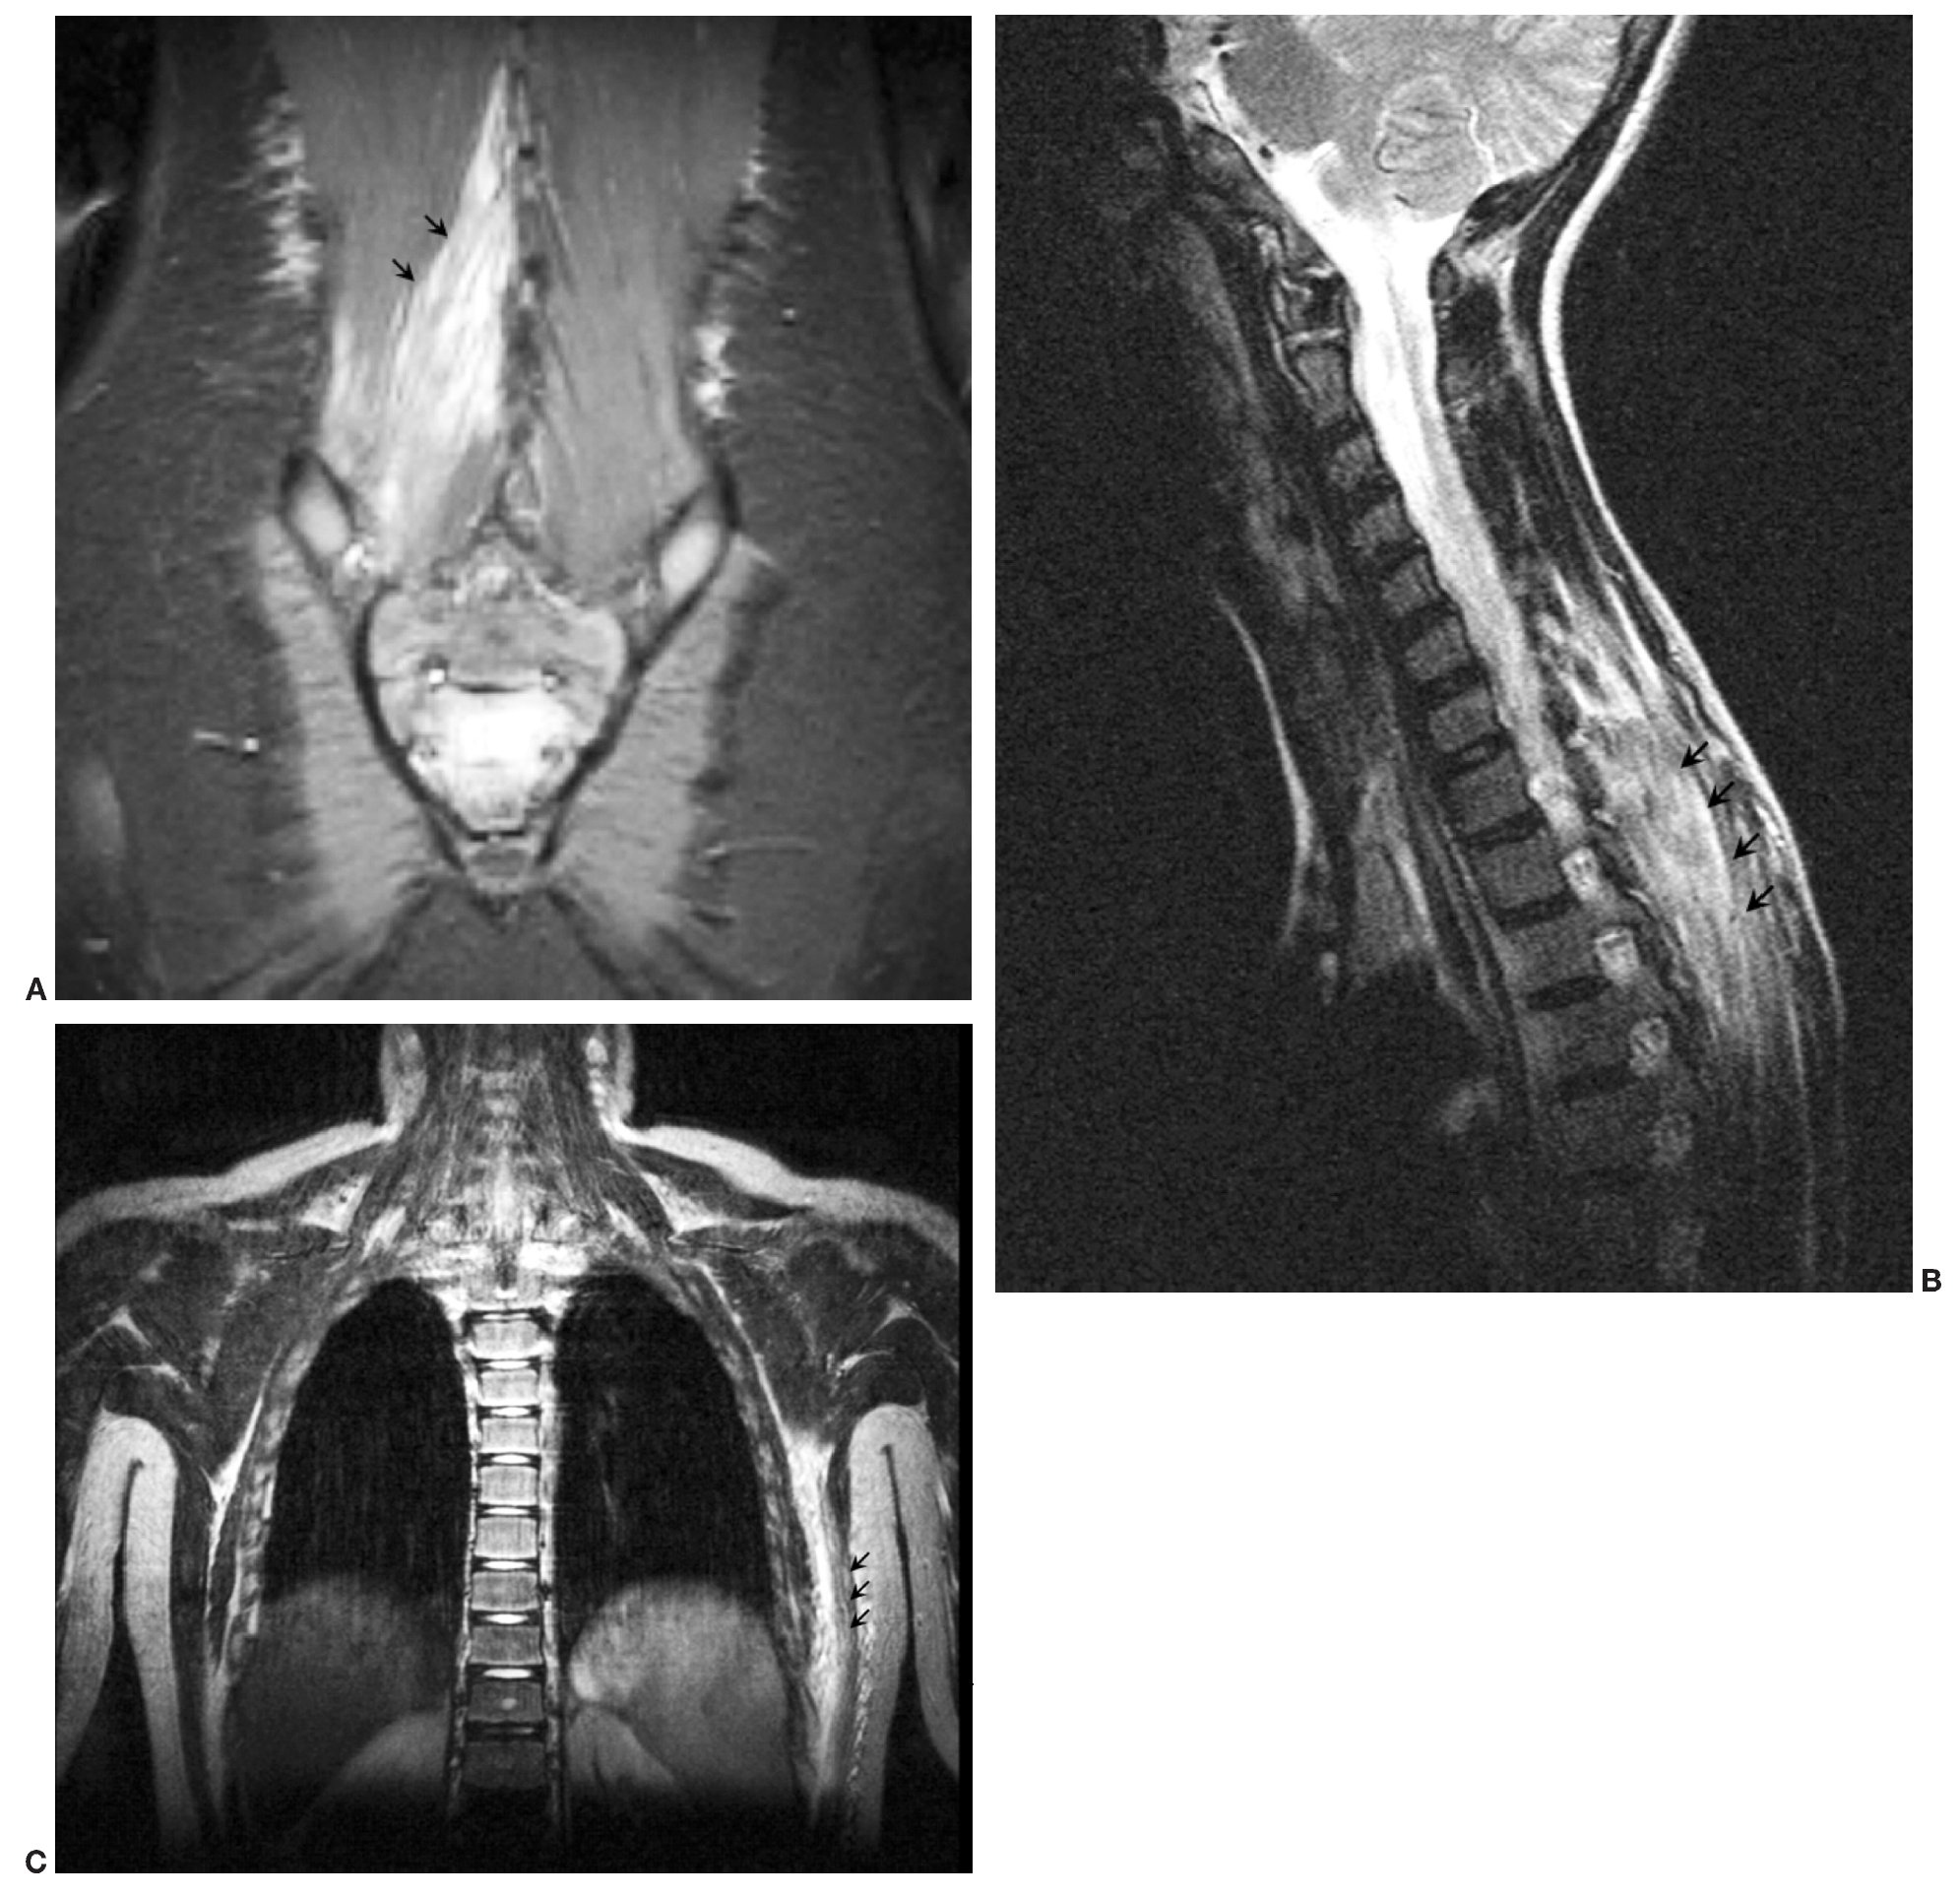

La piomiositis puede afectar a un músculo (fig. 2A) o a un grupo muscular2,4,12,15. Los músculos más comúnmente afectados son los del muslo y la región de la cadera: glúteos, aductores, obturador y psoas ilíaco (fig. 2B). La afectación preferente a este nivel hace que muchas veces el diagnóstico diferencial de la piomiositis sea extenso y se realice con artritis séptica, sinovitis transitoria, osteomielitis y/o procesos intraabdominales (apendicitis)16,17. En nuestra serie se evidencia esta predominancia, encontrando sólo tres casos de localización atípica, que afectaban a los músculos dorsal ancho, musculatura paravertebral cervical y lumbar (fig. 3).

Fig. 3. (A) Localización atípica de la piomiositis. La secuencia coronal STIR revela la afectación de la musculatura lumbar paraespinal derecha. (B) Localización atípica de la piomiositis. Secuencia sagital STIR que muestra la hiperseñal de la musculatura paraespinal dorsal, romboides y erectores de la columna. (C) Localización atípica de la piomiositis. Secuencia coronal STIR con hiperseñal del músculo dorsal ancho.